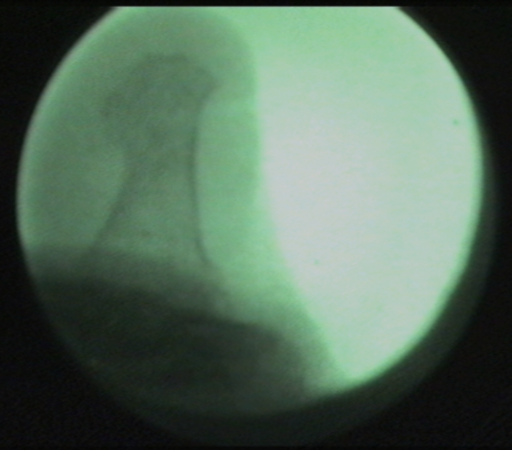

Imagen fluoroscópica de la exóstosis del 5º dedo